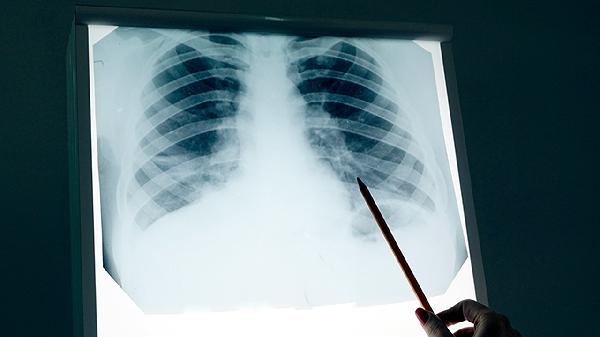

骨质被癌细胞侵蚀后强度下降,轻微外力即可引发骨折,好发于承重骨如椎体和股骨。X线显示虫蚀样骨质缺损,骨折后可能出现肢体畸形或活动受限。脊柱压缩性骨折可导致身高缩短或驼背。